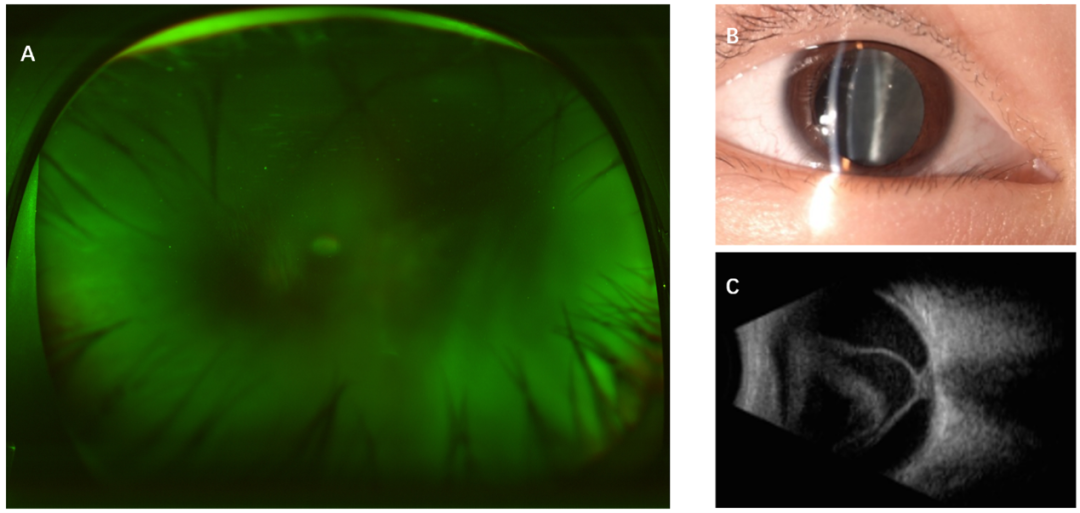

这番话引起了沈丽君警惕,结合患儿目前的眼部情况,高度怀疑他是感染了寄生虫导致的眼底病变。考虑到小希已出现视网膜脱离,沈丽君很快给安排了手术,并在术中取了眼内液体进行检验。果不其然,检测报告显示“眼弓蛔虫感染”,证实患儿视力急剧下降的“元凶”很可能来自宠物。

医院供图

弓蛔虫幼虫的游走性极强,一旦侵入眼部,会引发眼内炎症、玻璃体混浊、视网膜病变等多种问题,轻则导致视力下降,重则可能造成永久性视力损害,甚至致盲。很多家长对这种眼病知之甚少,而孩子常常不会表述,往往等孩子视力明显受损才就诊,此时眼部组织已遭损伤,大大增加了治疗难度。